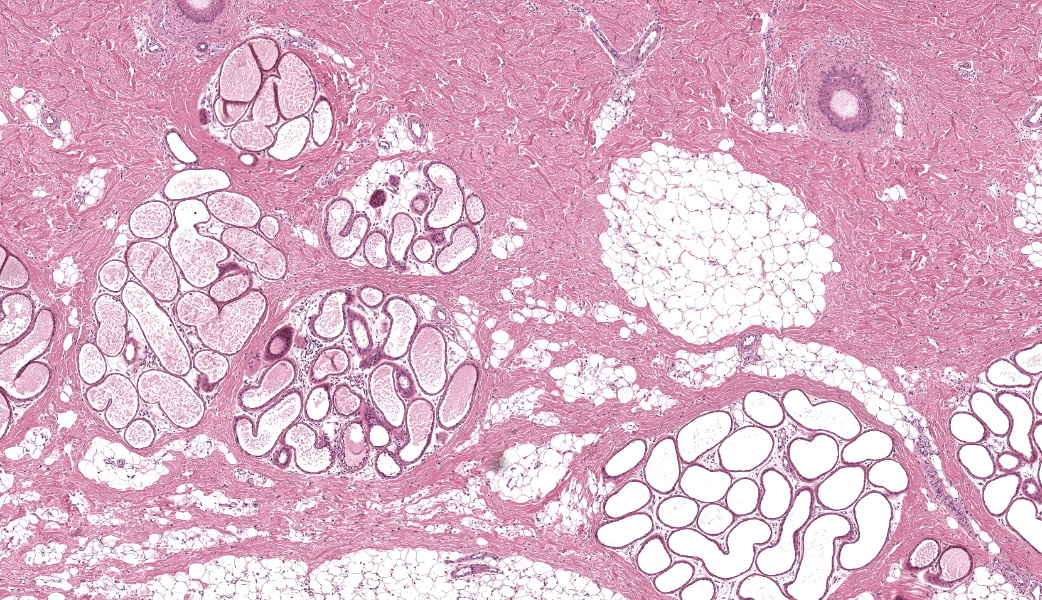

Haired skin (dorsal nose, three sections): Within the deep dermis and subcutis there are multiple well delineated clusters of variably distended apocrine glands with sinuous cystic cavities and partial tubular folding, which expand and replace dermal adipose tissue and muscle . Most of the clustered cysts are lined by a single layer of flattened columnar epithelial cells without apical blebbing. Adjacent smaller clusters of lesser distended glands exhibit one to several layers of more cuboidal epithelium. The outer layer of the cyst wall consists of thin layers of myoepithelial cells. Many gland lumina contain pale eosinophilic secretory product. Surrounding tissue and stroma comprises mild lymphoplasmacytic infiltrates.Focally in the mid dermis and associated with a hair follicle there is a localized, well demarcated focus of moderate mixed cellular inflammation composed of macrophages, neutrophils and lesser lymphocytes and plasma cells. These encase numerous distorted and/or ruptured apocrine glands, infiltrate their epithelium and are present within the lumen of remaining glandular structures (foreign body type reaction). Macrophages frequently contain cellular debris.

Skin: cystic distention of apocrine glands, diffuse, severe, with compression of adjacent muscle tissue consistent with cutaneous apocrine cystomatosis.Skin: hidradenitis and dermatitis, focally extensive, moderate, chronic, mixed cellular with apocrine gland rupture (foreign body type reaction).